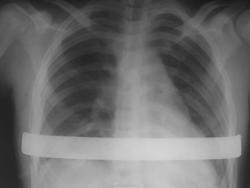

Воронкообразная деформация грудной клетки после пластики по Нассу.

метод Насса (миниинвазивная коррекция воронкообразной деформации грудной клетки). В англоязычной литературе данная операция называется как Nuss procedure или MIRPE (Miniinvasive repair of pectus excavatum). Во время операции производится два небольших разреза сбоку. В эти разрезы устанавливается одна-две металлические пластины, которые выпрямляют грудину и фиксируют ее в нужном положении. По прошествии 3-4 лет пластину вынимают, при этом правильная форма грудной клетки сохраняется. Операция проводится под общим наркозом. После оперативного вмешательства пациент проводит в стационаре около недели. В течение месяца необходимо соблюдать щадящий режим – разрешены только непродолжительные прогулки по городу. В течение трех первых месяцев не рекомендуется заниматься спортом. Однако, уже после 6 месяцев пациент полностью реабилитируется и может вернуться к обычной жизни. Пластина по прошествии этого времени почти не ощущается, болевой синдром больше не беспокоит.

Факт коррекции по прямой проекции констатировать сложно, надо боковую. А вот констатировать отсутствие пневмоторакса, который часто бывает как осложнение операции, вполне можно. Видимо, этого и хотят.

Сформулируем вопрос иначе, чего сейчас от нас хотят, кроме констатации факта коррекции деформации грудной клетки?